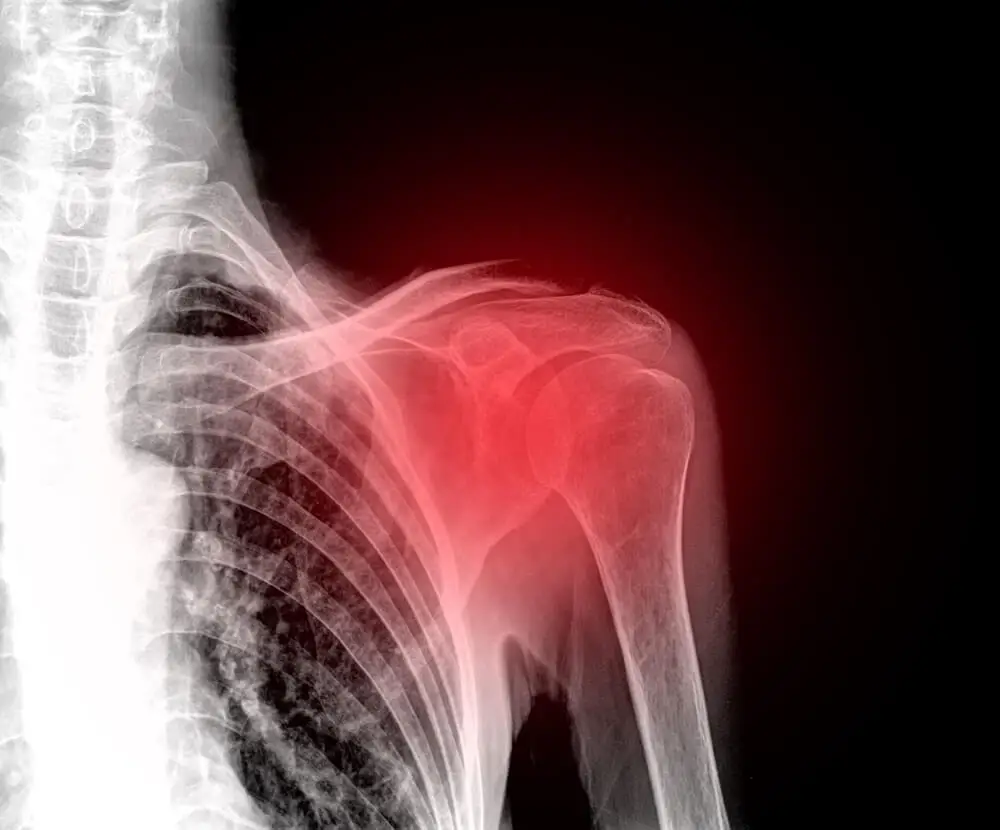

Ramię to zestaw stawów, które łączą ramię z tułowiem. Składa się z trzech kości (kości ramiennej, łopatki oraz obojczyka). Składa się również z kilku mięśni, więzadeł i ścięgien, które zapewniają mu stabilność i ruch.

Ze względu na szeroki zakres codziennych czynności, w które jest zaangażowany, łatwo jest podatny na drobne lub poważne obrażenia. Bóle barków mogą pojawić się po prasowaniu, myciu, przycinaniu ogrodu, intensywnym wysiłku fizycznym wymagającym poruszania rękami, uprawianiu sportu bez odpowiedniego rozgrzania, podnoszeniu dużych ciężarów itp.

Najczęstsze problemy z barkami

- Zwichnięcie: Zwichnięcie występuje, gdy czubek kości ramienia jest wypychany z panewki barkowej. Może się to zdarzyć z powodu nadużywania, skręceń lub uderzeń. Kiedy więzadła, ścięgna i mięśnie wokół barku stają się luźne lub naderwane, mogą się powtarzać zwichnięcia, powodując ból i niestabilność, jeśli ramię jest uniesione lub przesunięte do przodu.

- Zapalenie kaletki: kaletki działają jak podkładki, które zmniejszają tarcie między mięśniami i kośćmi. Nadużywanie barku może prowadzić do zapalenia kaletki, co powoduje ból i utrudnia wykonywanie codziennych czynności, takich jak czesanie włosów czy ubieranie się.

- Zapalenie ścięgien: ścięgna składają się z włókien tkanki łącznej i są odpowiedzialne za łączenie mięśni i kości. Zapalenie ścięgna jest zwykle spowodowane powtarzającymi się ćwiczeniami bez zachowania prawidłowej postawy lub może być związane z innymi urazami, takimi jak skręcenia.

- Złamanie: złamania są wynikiem złamania kości i zwykle występują w wyniku upadków lub urazów o dużej sile uderzenia, takich jak wypadki sportowe lub samochodowe. Powodują silny ból i stan zapalny.

- Choroba zwyrodnieniowa stawów rozwija się w wyniku postępującego zużywania się stawów i często wiąże się z naderwaniem mięśni i ścięgien oraz infekcją. Objawia się stanem zapalnym, bólem i sztywnością.

- Reumatoidalne zapalenie stawów to choroba autoimmunologiczna, która powoduje stan zapalny stawów i objawia się bólem, obrzękiem, zaczerwienieniem i deformacją.